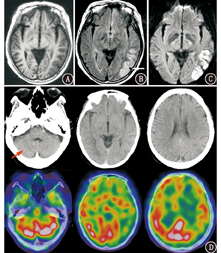

患者女,62岁,因言语不清伴右眼视物不清3 d就诊。血常规、肝肾功能及凝血全套检测均正常。体格检查:血压155/71 mmHg(1 mmHg=0.133 kPa),神清,格拉斯哥昏迷评分(Glasgow coma scale, GCS)15分,定向力正常,口齿不清;双侧瞳孔直径3.0 mm,光反应灵敏,两侧眼球活动无异常,粗测视野右侧同向偏盲;两侧额纹对称,两侧鼻唇沟基本对称,伸舌居中;右下肢可疑5级-,余肢体肌力5级,两侧肌张力无异常,两侧腱反射对称阳性,巴宾斯基征阴性。患者既往无高血压、冠状动脉硬化性心脏病及糖尿病史。头部CT检查示左枕叶低密度,诊断为脑梗死。MRI平扫示左颞叶、枕叶见片状异常信号;T1加权成像(weighted imaging, WI;图1A)呈低信号,局部脑表面见点状、线样高信号,T2液体衰减反转恢复(fluid attenuated inversion recovery, FLAIR)序列成像(图1B)示左颞叶、枕叶斑片状高信号,局部脑表面见点状、线样高信号,即"常春藤"征,并可见粗大流空血管信号,左额叶、颞叶、顶叶及枕叶皮质下轻度信号增高;弥散加权成像(diffusion weighted imaging, DWI;图1C) (b=1 000 s/mm2)示左颞叶、枕叶皮质片状高信号。99Tcm-双半胱乙酯(ethylcysteinate dimer, ECD)SPECT/CT脑血流灌注显像(图1D)示,左额叶、颞叶、顶叶及枕叶大范围脑血流灌注减低区,局部脑血流(regional cerebral blood flow, rCBF)为26.75~37.91 ml·100 g-1·min-1,右小脑半球局部脑血流灌注减低,提示交叉性小脑失联络。数字减影血管造影(digital subtraction angiography, DSA;图2)示左侧大脑半球弥漫性异常血管增生,病灶弥漫性分布,供血动脉累及左大脑前动脉、左大脑中动脉及左大脑后动脉,左颈外动脉造影额颞部可见多处硬膜血管向颅内代偿。最终诊断:增殖性脑血管病(cerebral proliferative angiopathy, CPA),左颞叶、枕叶脑梗死。予营养神经、改善微循环等保守治疗后,患者症状好转并出院。

CPA的诊断主要依赖于DSA,其表现为累及整个脑叶甚至整个大脑半球的弥漫性增生的血管网,呈"泥浆样"改变,无优势供血动脉及引流静脉或与血流相关的动脉瘤,病灶边界不清,存在混合的正常脑实质[1]。99Tcm-ECD SPECT/CT脑血流灌注显像可计算出不同部位的rCBF,而同机CT能弥补SPECT图像组织分辨率低、解剖结构不清晰的不足,从而提高对缺血性脑血管病的诊断能效[4]。本例SPECT/CT脑血流灌注显像显示,患者左大脑半球弥漫rCBF减低,范围明显大于常规MRI异常信号区,与文献[5]报道一致,且负荷脑血流灌注显像提示脑血流储备功能降低,CPA受累区域为低灌注状态,血流动力学特点更接近烟雾病[5,6]。因此,对于疑似脑卒中的患者,当SPECT/CT脑血流灌注显像所示缺血范围明显大于CT和(或)MRI所示时,或显像呈现整个大脑半球、多个脑叶大范围的明显脑缺血改变时,需考虑CPA的可能,建议进一步行DSA检查明确诊断。本例SPECT/CT脑血流灌注显像还观察到交叉性小脑失联络现象,而CT及MRI均未显示,也体现了脑血流灌注功能显像的优势。

本例MRI受累脑表面FLAIR序列显示"常春藤"征,这是烟雾病较特征性的影像学征象,其意味着脑缺血更严重或脑血管反应性下降更明显,动态观察血运重建术后"常春藤"征的变化可有效评估手术疗效[7]。